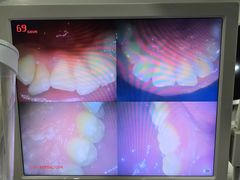

• 土豆口腔(凤凰北总店)

咕咕嗵 | 24-02-08